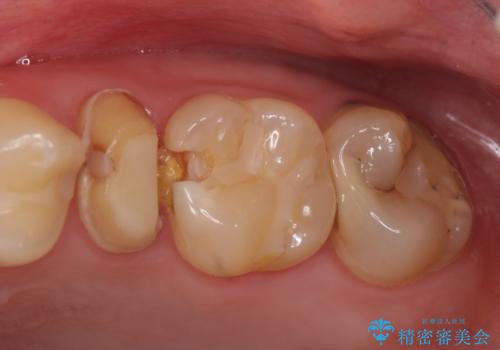

- 左上の歯が痛くてものが咬めないといらっしゃった方の症例です。

左上6は自発痛および持続痛を認めたため根管治療後、オールセラミッククラウンによる補綴を行いました。

左上7は冷水痛のみだったため、慎重に虫歯の除去を行い症状がないことを確認後、オールセラミッククラウンによる補綴を行いました。

左上5は再根管治療後、オールセラミッククラウンによる補綴を行いました。